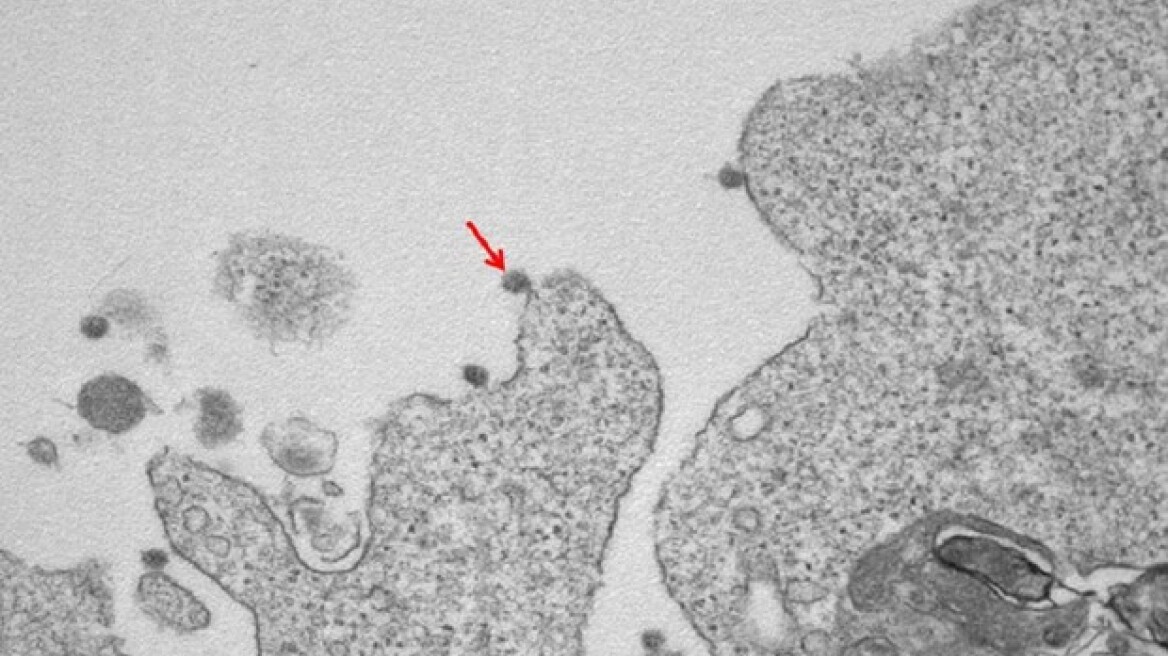

Τις πρώτες φωτογραφίες του κορωνοϊού, από κρούσματα της Λομβαρδίας, έδωσε στη δημοσιότητα το κρατικό πανεπιστημιακό νοσοκομείο Sacco του Μιλάνου, όπως αυτές «τραβήχτηκαν» από ερευνητές του εργαστηρίoυ λοιμωδών νοσημάτων, που διαθέτει.

Η ομάδα ερευνητών του εργαστηρίου, σε συνεργασία με το τμήμα ανατομικής παθολογίας του νοσκομείου, κατάφερε να απομονώσει τον ιό SARS-CoV-2 και να τον «φωτογραφίσει» μέσω ηλεκτρονικού μικροσκοπίου. Οι εικόνες που δημοσιεύτηκαν, δείχνουν τα ιικά σωματίδια που προσκολλώνται στις κυτταρικές μεμβράνες, μέσω της «κορώνας» των γλυκοπρωτεϊνών που διαθέτουν.

Συγκεκριμένα, η πρώτη φωτογραφία, που έχει μεγέθυνση 30000Χ «παρουσιάζει τα ιικά σωματίδια του Sars-CoV-2 να είναι προσαρτημένα στις επιφανειακές μεμβράνες και στο εσωτερικό κυττάρου».